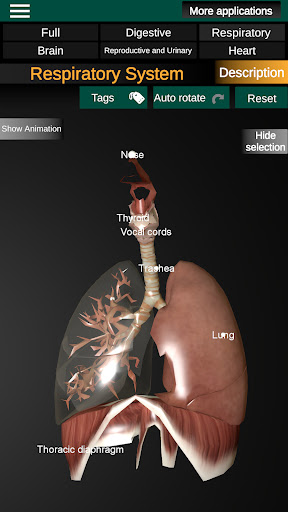

Internal Organs in 3D Anatomy لـ Vodafone Smart N9 Lite

(الأجهزة الداخلية في)

Internal Organs 3D Anatomy 3.4

يمكنك هنا تنزيل ملف حزمة تطبيق أندرويد "Internal Organs 3D Anatomy" الخاصة بجهازVodafone Smart N9 Lite مجانًا، نسخة ملف حزمة تطبيق أندرويد - 3.4 للتحميل على Vodafone Smart N9 Lite اضغط ببساطة على هذا الزر. إنه سهل وآمن. نحن نقدم فقط ملفات حزمة تطبيق أندرويد الأصلية. إذا انتهكت أية مواد موجودة في الموقع حقوقك قم بإبلاغنا من خلال